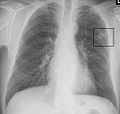

Der Unterschied zwischen der überlagerungsfreien Darstellung in der medizinischen Tomografie und einer Projektionsabbildung ist in den nachfolgenden Abbildungen illustriert. In Projektionsverfahren wie der Radiografie (gewöhnliche Röntgenuntersuchung) wird ein Schattenbild aufgenommen, auf dem sich mehrere Strukturen überlagern, wenn sie im Strahlengang hintereinander liegen. Beispielsweise überlagern beim konventionellen Röntgenbild die Weichteile der vorderen und hinteren Brustwand und die knöchernen Strukturen des Thorax die Lungenstrukturen. Dies würde die Diagnose eines Lungentumors (z. B. Bronchialkarzinom) erschweren. Jedes CT- oder MRT-Schnittbild vom Thorax zeigt dagegen nur eine 0,5 bis 10 mm dicke Schicht, die praktisch überlagerungsfrei ist.

Röntgenbild (Projektionsbild) eines kleinen peripheren Bronchialkarzinoms im linken Oberlappen -